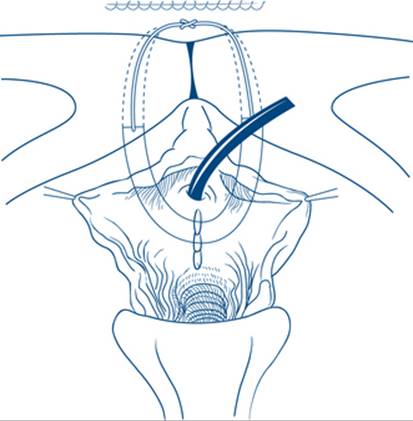

For patients with acute retention requiring continuing drainage, a balloon catheter, preferably made of silicone rubber, is desirable. The catheter should not be so large as to hinder free drainage of urethral secretions and a 12F Foley catheter is satisfactory in an adult in most cases. If a Foley catheter cannot be passed, a thinner (6–8F) plastic Gibbon catheter may succeed in navigating a stricture, but often if stricture is present direct visualisation will be needed or suprapubic drainage. In the instance of a large prostate, it is often easier to pass a larger size 16 or 18F catheter with a little more inherent rigidity than a smaller catheter. It will more easily pass through the curve of the bulbar urethra without coiling up than might a smaller bore catheter. If urethral catheterisation for urinary retention is unsuccessful, the distended bladder can be drained suprapubically by percutaneous insertion of a balloon suprapubic catheter. Again, an experienced operator is required and kits based on Seldinger techniques now exist to ensure safe suprapubic puncture without traversing other organs or vessels. Any patient who has had a prior laparotomy or has a lower midline abdominal incision should have a preplacement ultrasound to mark the site of safe puncture (Fig 9.9).

Figure 9.9 Catheterisation of a distended bladder by percutaneous puncture